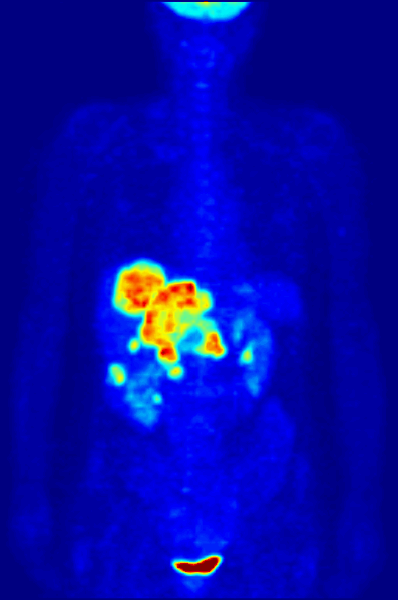

• PET Scan (Positron Emission Tomography)